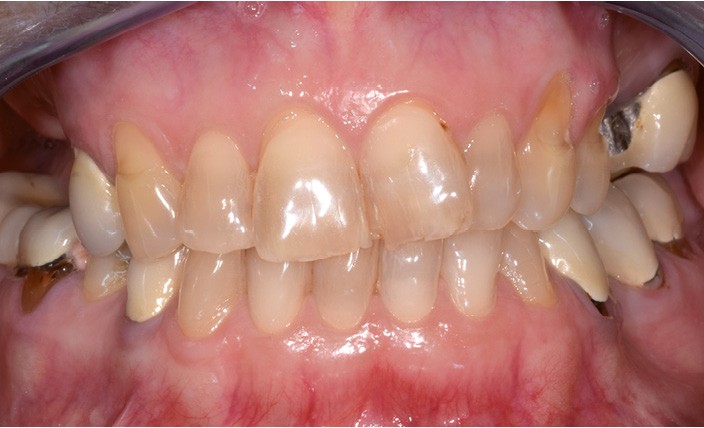

Une patiente d’une cinquantaine d’années consulte pour refaire sa prothèse amovible partielle métallique maxillaire, source d’inconfort (fig. 1 et 2).

Nous sommes en présence, au maxillaire, d’un édentement de classe 2 subdivision 1 de moyenne étendue (fig. 3). La problématique propre à ce cas de classe 2 est le soulèvement lors de la mastication d’aliments mous/collants et l’asymétrie. Cependant, la présence d’une subdivision compense en partie l’asymétrie. La recherche d’appuis les plus antérieurs possible à l’axe de rotation pour contrer le mouvement de soulèvement postérieur est également…